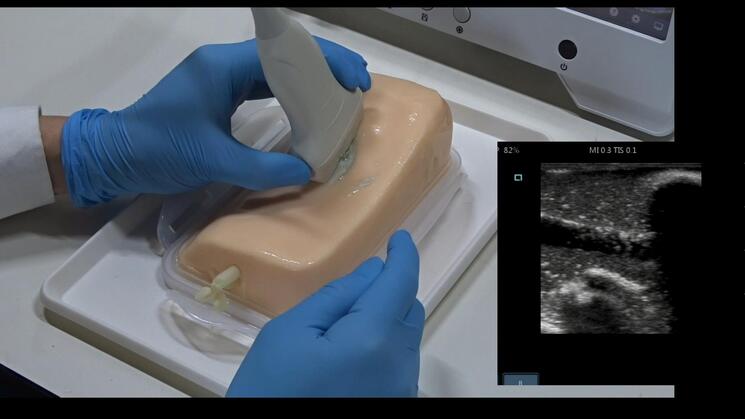

Amazon.co.jp: 超音波ガイド下穿刺オンラインセミナー CVC基本。Amazon.co.jp: 超音波ガイド下穿刺トレーニングモデル AGL330。アルファバイオ株式会社 超音波ガイド下穿刺トレーニングで。

超音波ガイド下穿刺オンライントレーニングに使用します。アルファバイオ株式会社 超音波ガイド下穿刺トレーニングで。 オンラインセミナーは、こちらのキットと、施設内の超音波装置があれば、だれでも簡単に受講できます。後期研修医がおさえておきたい泌尿器科疾患TOP30。 商品の保存は直射日光の当たらない冷所で保存してください。腎・泌尿器 成人看護学 8 教師用献本。 購入後なるべく早くご使用ください。精神看護の展開 系統看護学講座 専門分野2―〔23〕。